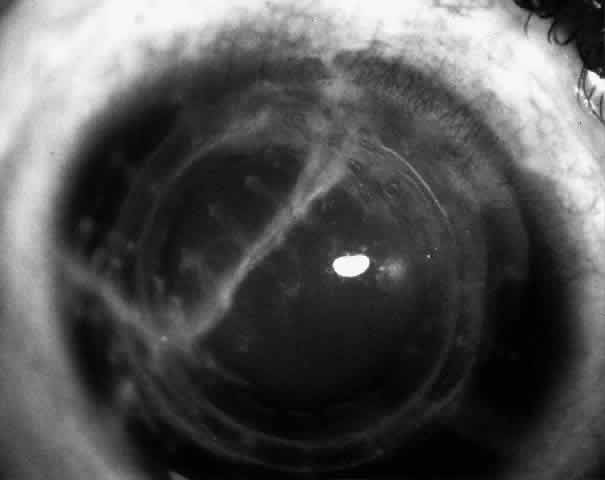

Children who have traumatic cataracts with corneal lacerations are well served by this procedure because the injury often destroys the capsular support that can be used to stabilize an intraocular lens.16–18 The epikeratophakia graft provides structural support for the weakened cornea and minimizes the induced irregular and regular astigmatism, in addition to correcting the optical error (Figs. 3 AND 4).

Fig. 4. Same patient as in Figure 11, with epikeratophakia lenticule in place 3 months after surgery. (Morgan KS, Ellis GS, Marvelli TL, Arffa RC: Epikeratophakia in children. with traumatic cataracts. J Pediatr Ophthalmol Strabismus 23:108–113, 1986)